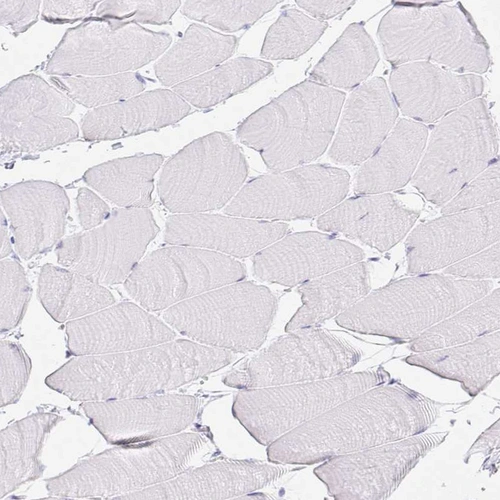

Immunohistochemistry analysis in human pancreas and skeletal muscle tissues using HPA016668 antibody. Corresponding GP2 RNA-seq data are presented for the same tissues.